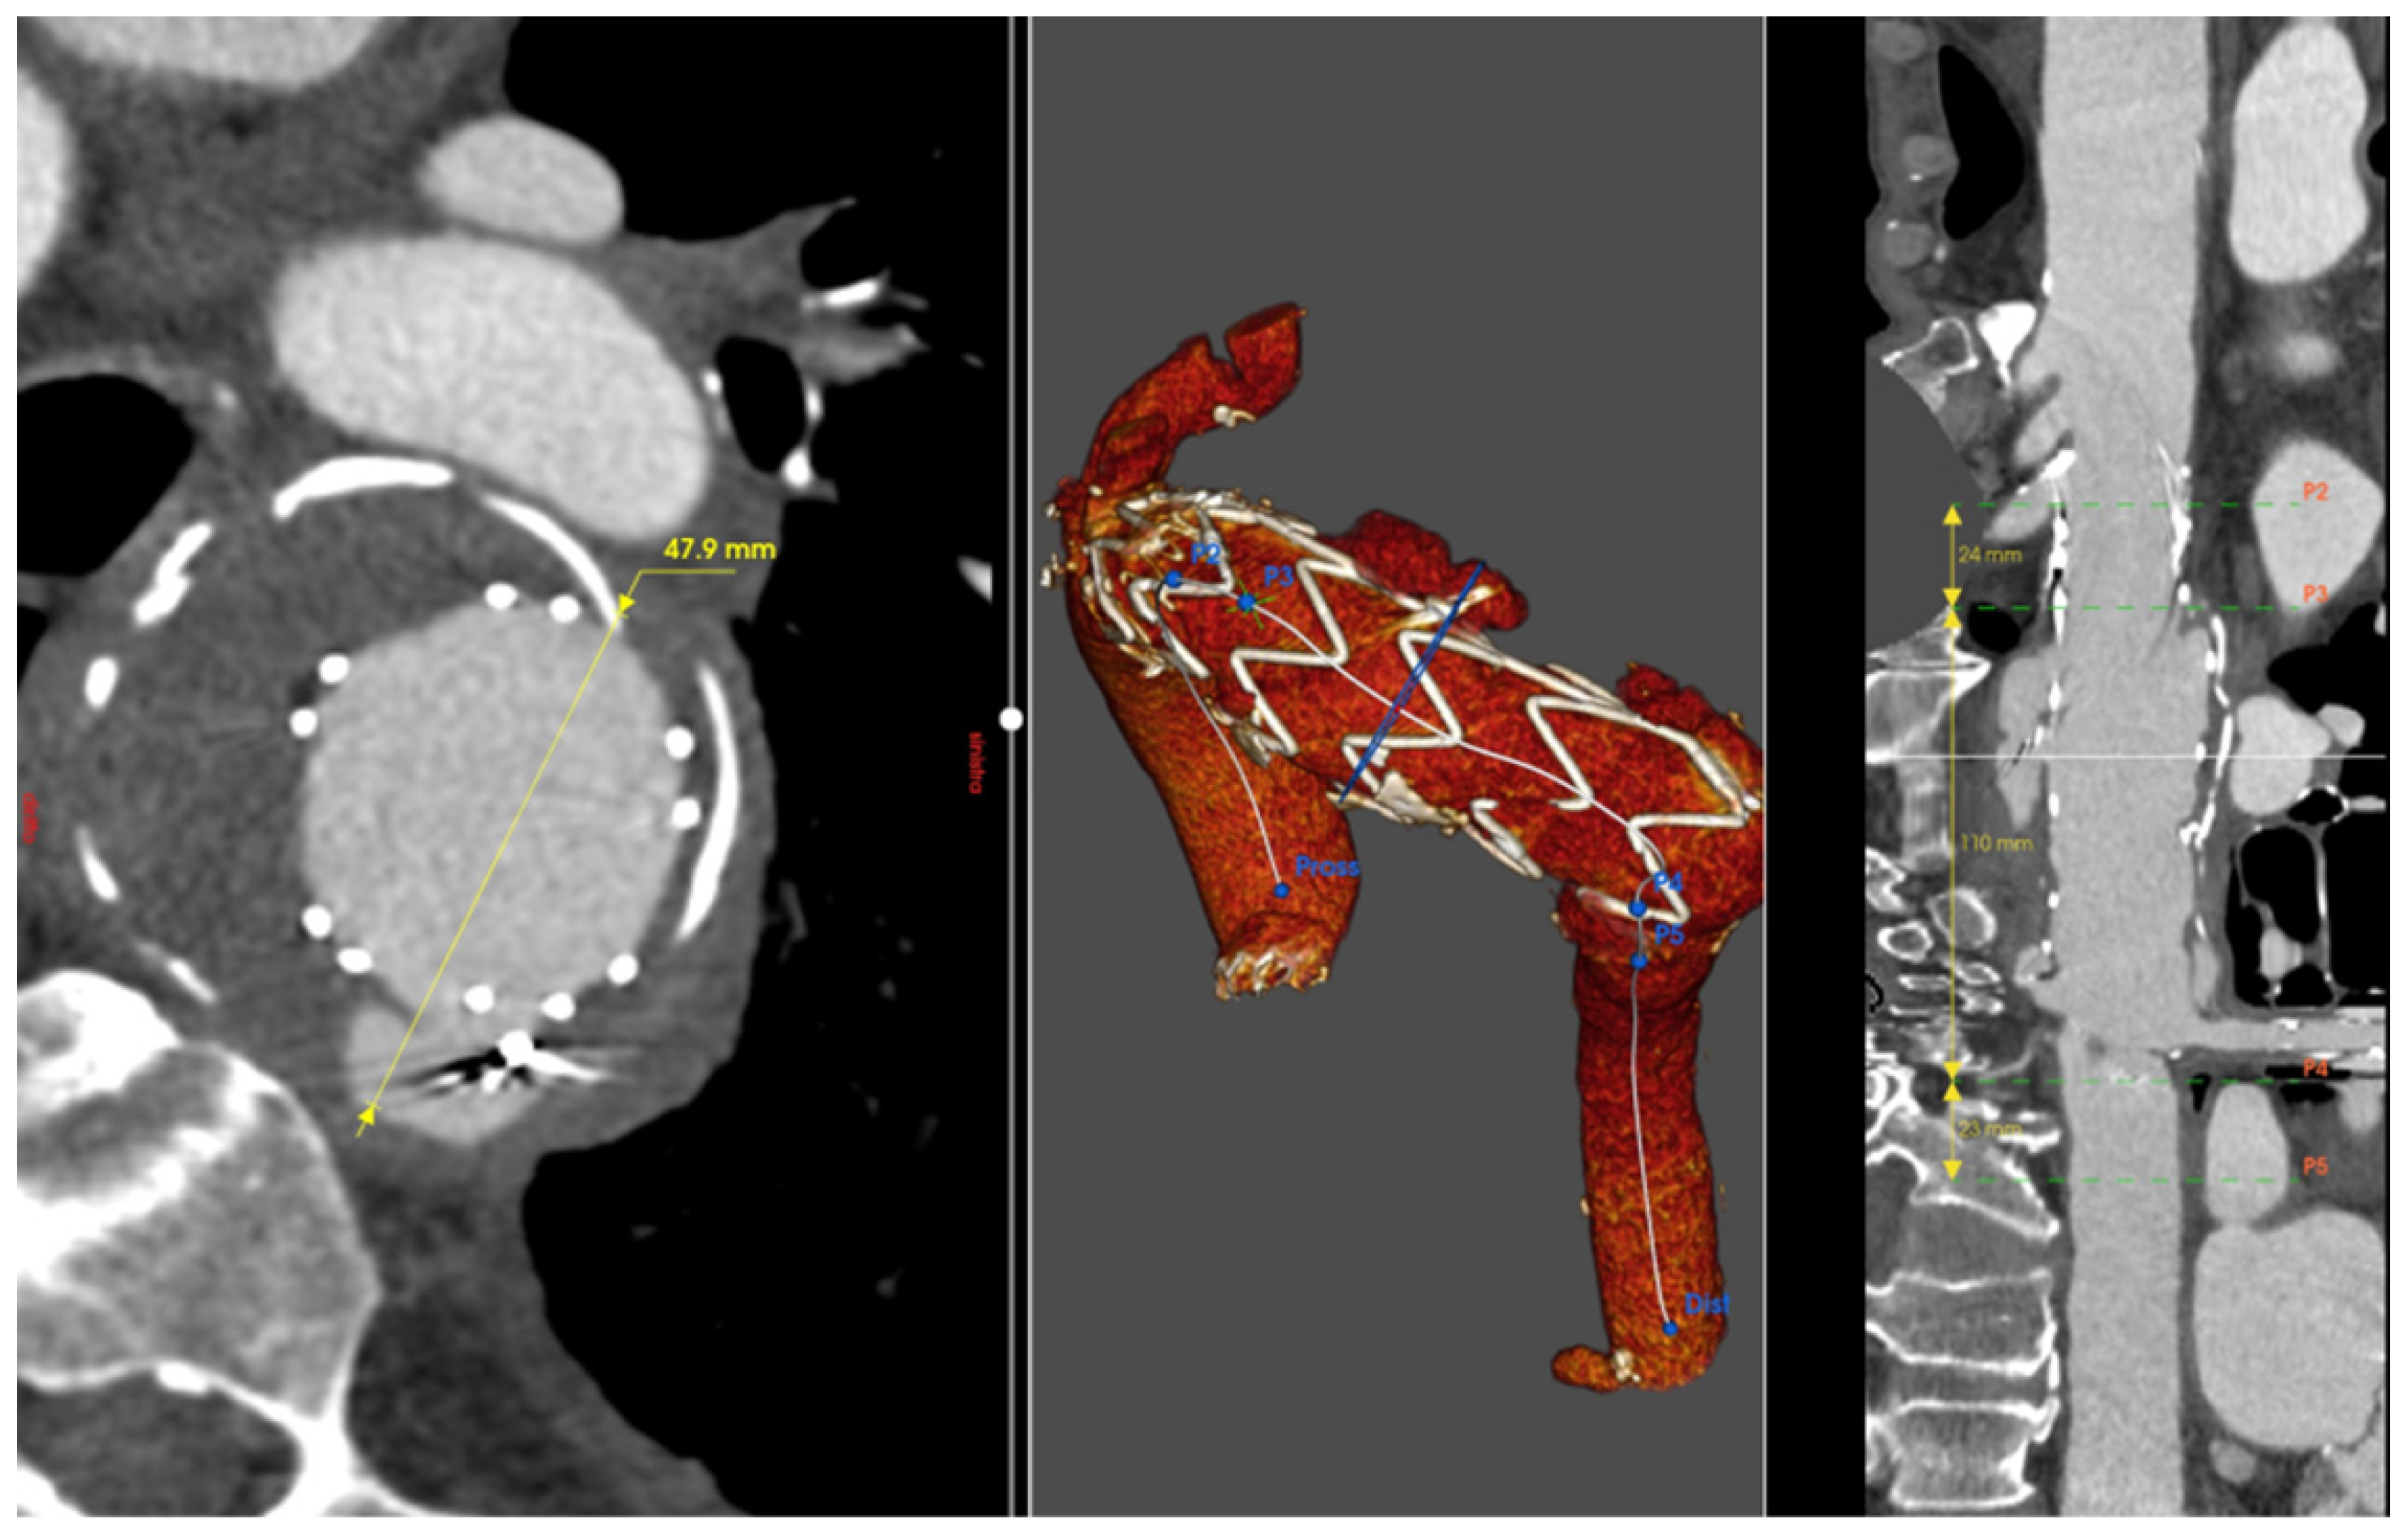

Figure 3.

Patient 3’s Computed Tomography Angiography showing the evolution of the type B dissection with an enormous aneurysm of 75 mm in Zone 3 (A). Three-dimensional reconstruction of the result after the frozen elephant trunk operation (B). After one month, the patient was treated with another TEVAR in the descending aorta.

A 66-year-old gentleman presented with an aneurysm of 75 mm of the distal aortic arch and proximal descending thoracic aorta just below the origin of the subclavian artery, in the context of chronic type B aortic dissection previously managed conservatively. Further dilatation of the descending thoracic aorta with kinking at the diaphragm made the anatomy more challenging. Aneurysmatic dilatation of the ascending aorta precluded an endovascular option alone. Therefore, aortic arch replacement was considered a suitable approach [6]. A left common carotid–left subclavian artery extra-anatomical bypass was performed, followed by a frozen elephant trunk (FET) with Jotec E-Vita Open Neo 30-120 × 30 prosthesis 24 h later. The innominate and left common carotid arteries were re-implanted. Finally, significant disease of the left anterior descending coronary artery required grafting with the left internal mammary artery. The patient’s aortic pathology was further complicated by severe peripheral vascular disease, including total occlusion of the left external iliac artery and the right common iliac artery originating from the false lumen. Despite the unfavorable anatomy, a TEVAR (Terumo Relay Pro 32 × 32 × 155 mm) was performed, extending the distal landing zone to prevent caudal endoleak formation and exclude the aortic aneurysm. To address the type II endoleak originating from the left subclavian artery, a vascular plug was placed at its aortic origin, which completed the false lumen thrombosis of the Zone 4 aneurysm and the descending aorta. After a long and complicated postoperative course, the patient was discharged and continued with regular CTA follow-up, demonstrating clinical and anatomical stability (Figure 3).